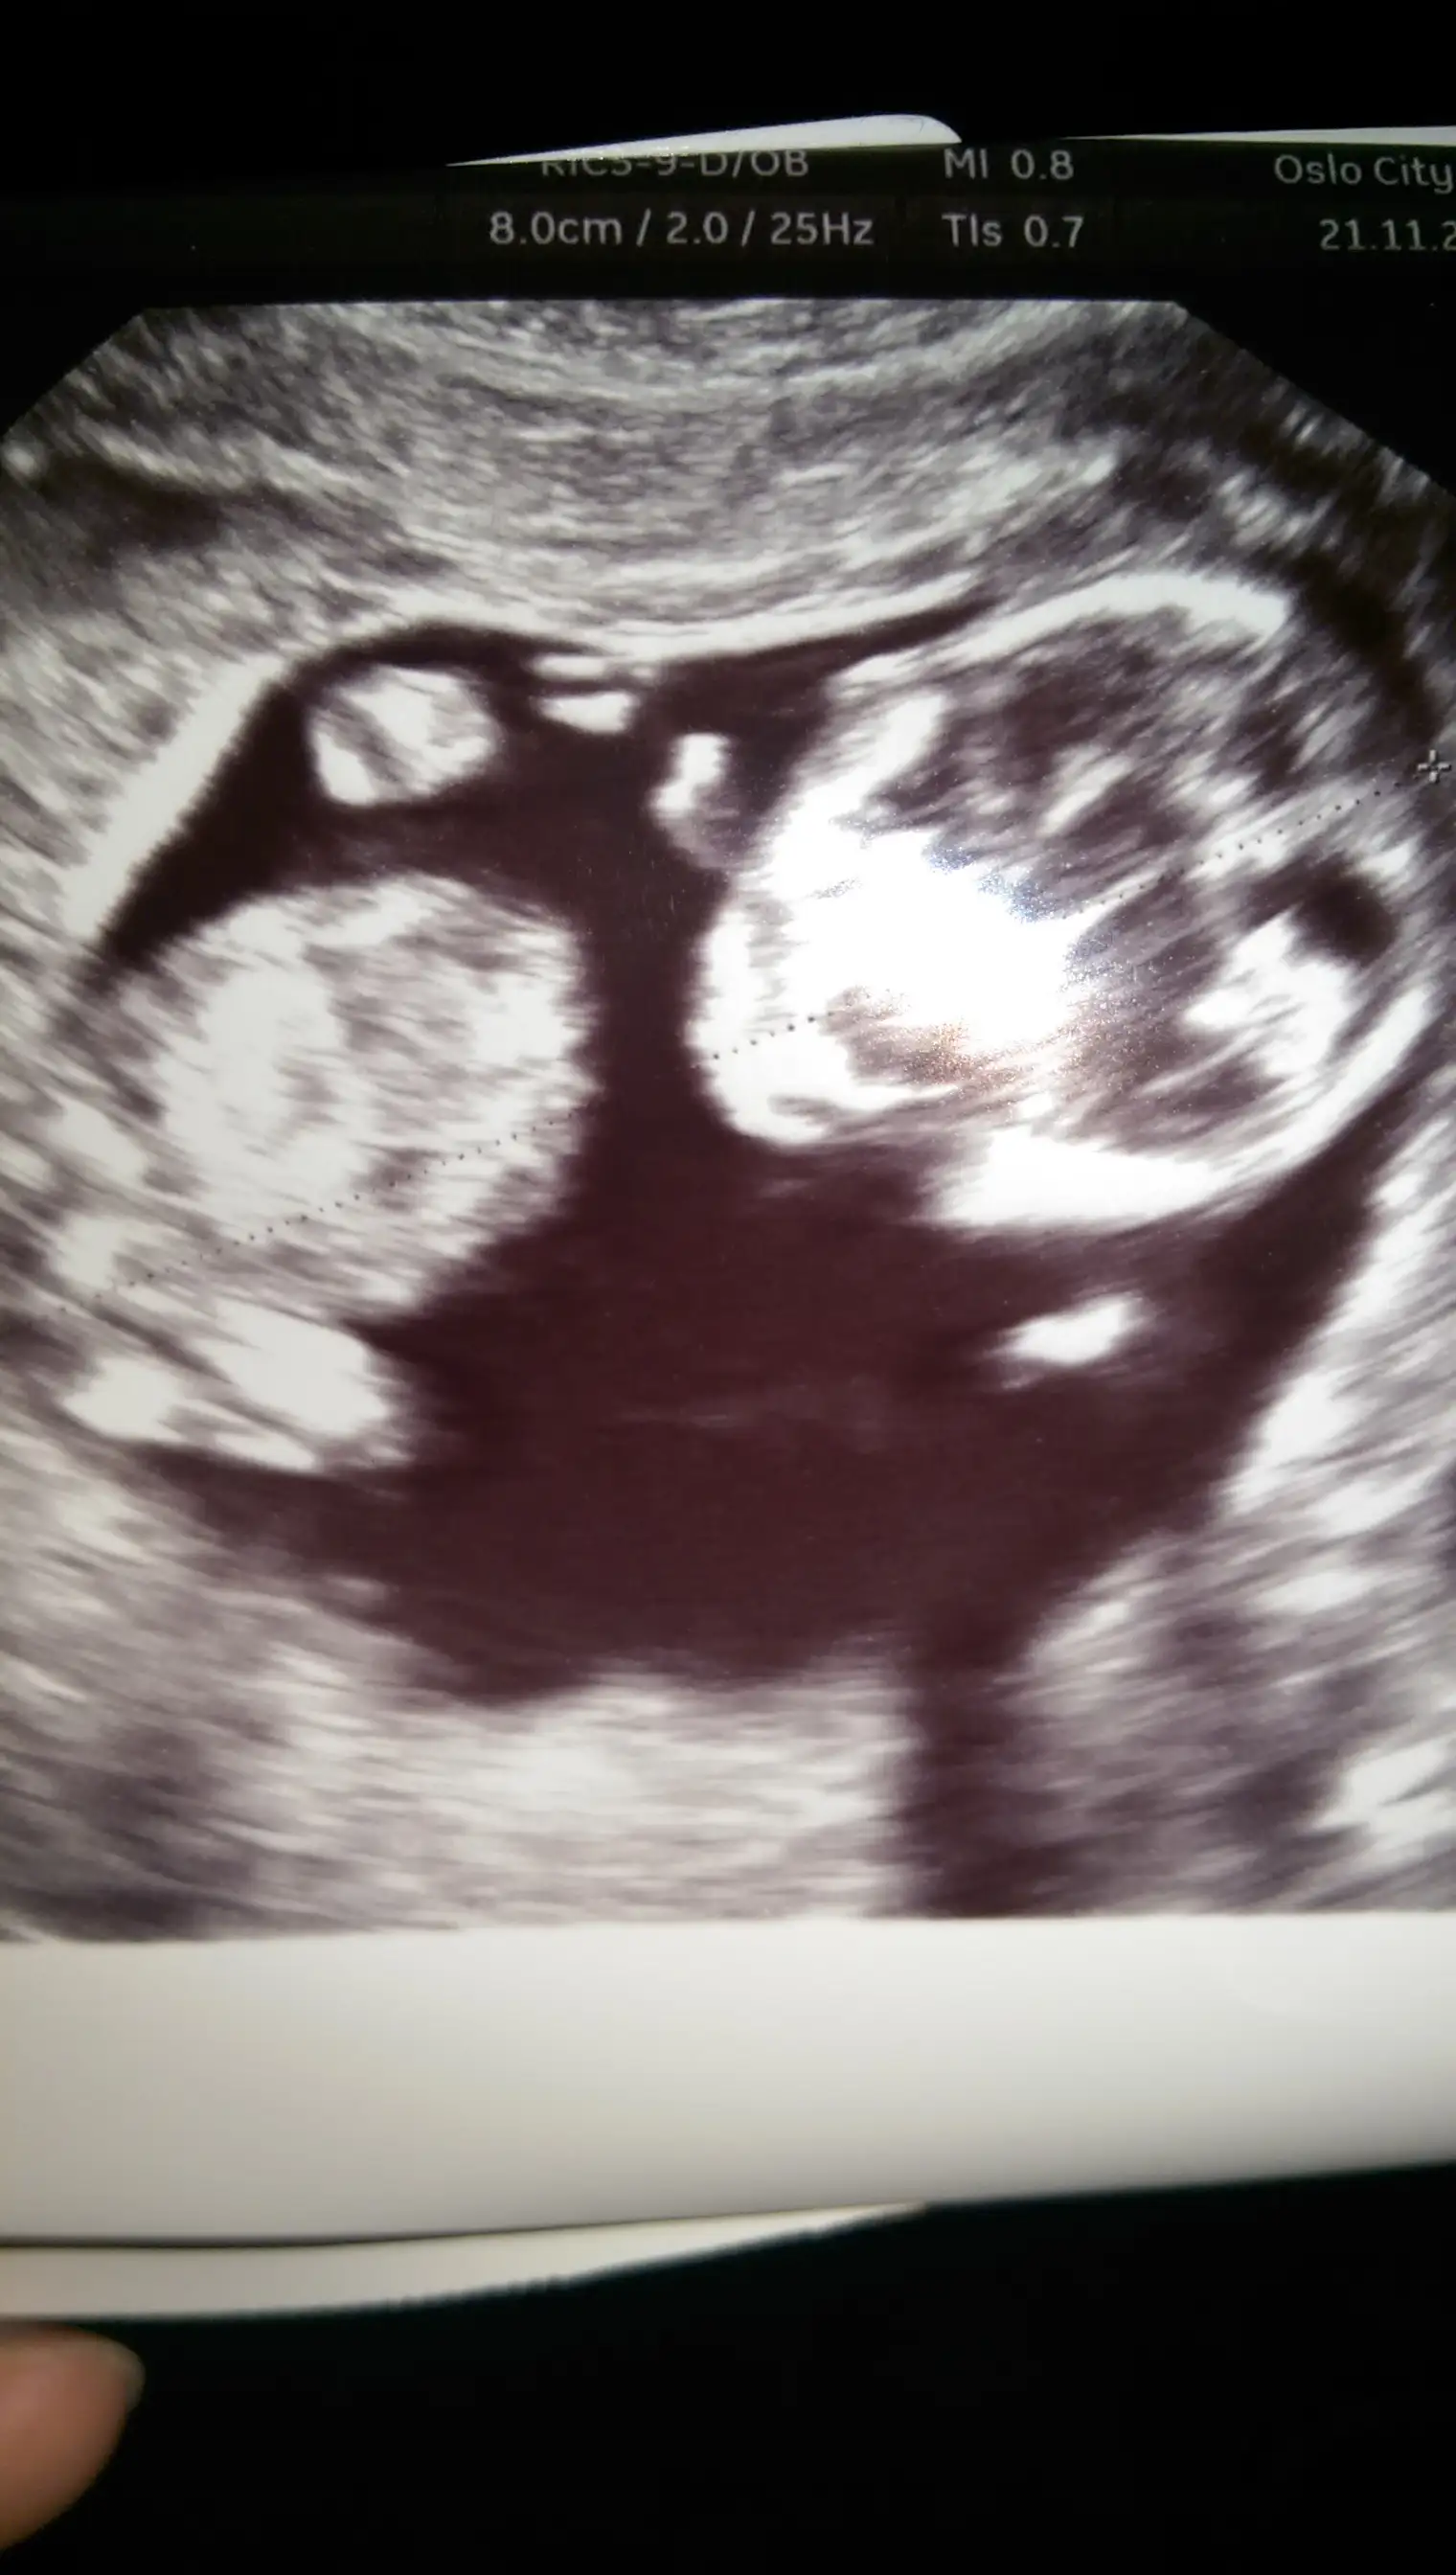

Selam kizlar biz doktordan geldik 12.haftamizi doldurduk hatta bir hafta once gidiyormusuz bi bakabilirmisiniz cinsiyet tahminine :) siz soledikten sonra bende doktorun tahminini solicem :) simdiden cok tsk ederim :KK66:

Denizkizi_ESra Canim KIz gibi geldi bana :) Anlamam ama kuru bir tahmin iste. Bu nub neyin nesi yaaa ...

Tahmin icin saol canim ama cinsiyet tahmini icin nub tan anlaman lazim :( bende anlamiyorum burdaki tecrubeli annisler anlayanlar saolsun yardimci oluyorlar :)